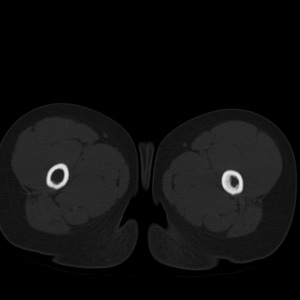

标题: PED1884:患者,男性,7岁。因右髋疼痛5天,而来院检查。 [打印本页]

标题: PED1884:患者,男性,7岁。因右髋疼痛5天,而来院检查。

因右髋疼痛5天,而来院检查。

我们考虑:1、骨皮质增厚症。2、畸形性骨炎。3、骨纤。

右髋疼痛,左侧病变,看来无症状。

支持左股骨上段骨纤维异常增殖症可能性大.